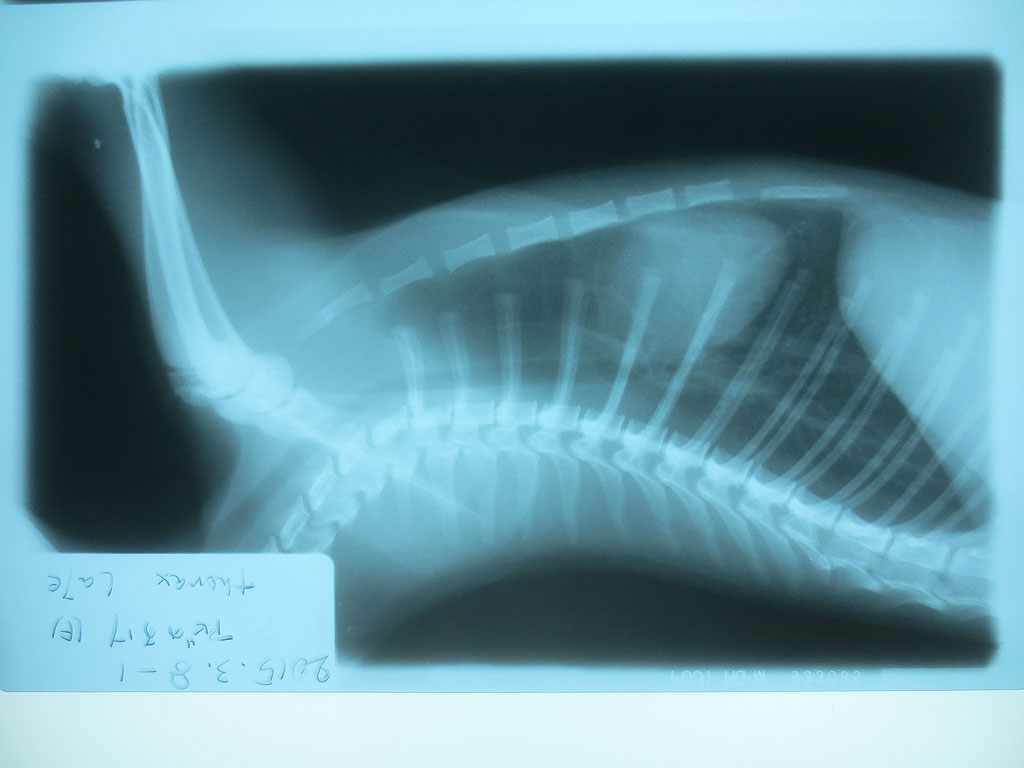

そして、レントゲンの現像も終わって、また診察室に呼ばれ、早速、レントゲンの写真を見せて頂いたのですが、いきなりですが、アビのすけの胃の中に異物が…。

紐とかだったらレントゲンに写らないそうなのですが、かなりはっきりと写っていて、何か、金属的なものを飲み込んでいるとの事…。

食パンの袋の口を結ぶ、芯に針金が入ったくるくるってひねって巻くやつの様だと先生はおっしゃったのですが、そんなものは部屋の中にはない筈なのですが、私が落としてしまったのかも知れず…。

全部で6枚、撮って頂いたのですが、後の5枚は、特に何も写っていなかったので、連続でアップさせて頂きます。